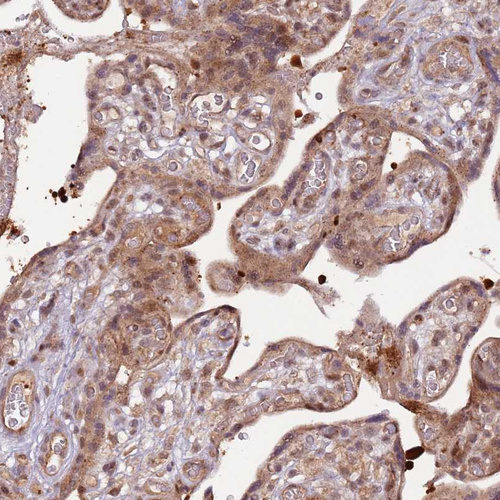

Immunohistochemical staining of human placenta shows moderate cytoplasmic positivity in trophoblastic cells.